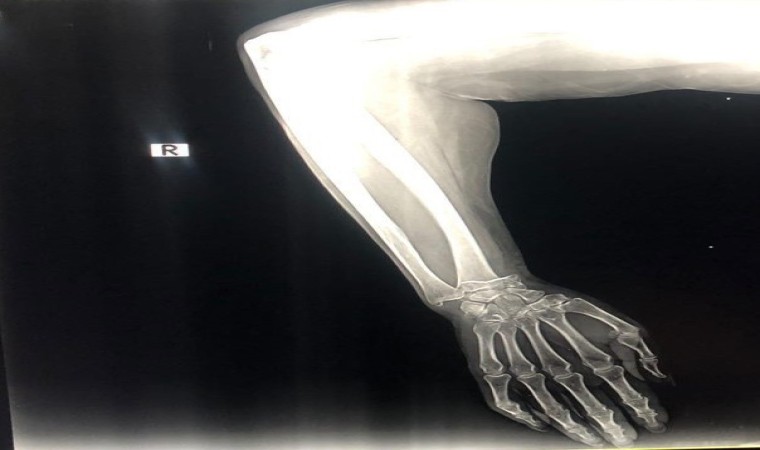

Olay, 4 Ağustos Cuma günü Kemer ilçesi Aslan Bucak Mahallesi Cuma pazarında yaşandı. Savaştan kaçıp Antalya’ya yerleşen Olena Buletsa (61), burada Şeyhmus Doğan ile yakın bir tarihte evlenen kızı Kateryna Buletsa’la (32) pazar alışverişine çıktı. Kızıyla birlikte yürüdüğü sırada dengesini kaybedip yere düşen Olena Buletsa’nın bileği kırıldı. Çevredekilerin durumu 112 Acil Çağrı Merkezine bildirmesi üzerine Buletsa ambulansla Kemer Özel Yaşam Hastanesine götürüldü. Burada iddiaya göre, sadece röntgen ve alçıya bin 680 dolar (günün kuruyla 44 bin 555 TL) fatura kesildi. Buletsa ve kızı bu parayı ödeyip evlerine döndü. Faturayı gören damadı Şeyhmus Doğan hastaneye gidip faturaya hastane çalışanları ve yetkililerine tepki gösterip itiraz etti. Olaydan bir gün sonrası ise 850 dolar Kateryna Buletsa’nın hesabına geri yatırıldı.

“Bir röntgen çekildi, ardından cerrah kolu ayarladı ve bir alçı uyguladı. Sonuçta doktor alçının geçici olduğunu ve ameliyat gerektiğini söyledi. Bize bin 650 dolarlık bir fatura verdiler. Operasyonun miktarını belirtmediler. Bütün bunların Ukrayna’da çok daha ucuz olacağını düşünüyorum. Alçı yaklaşık 30 dolara mal olacak ve ameliyat yaklaşık 800 dolara mal olacak. Ukrayna’da bir savaş var. Oradan kaçıyoruz. Yardım istedik. Ve bu hastanenin hizmetleri için çok büyük parayı ödedik. Ukrayna’da alçı fiyatı yaklaşık 30 dolar. Kısacası, acil bakım, enjeksiyon, röntgen ve geçici alçı için bin 650 dolar aldılar. Annem Ukrayna’ya gidip muayene olacak” diye konuştu.